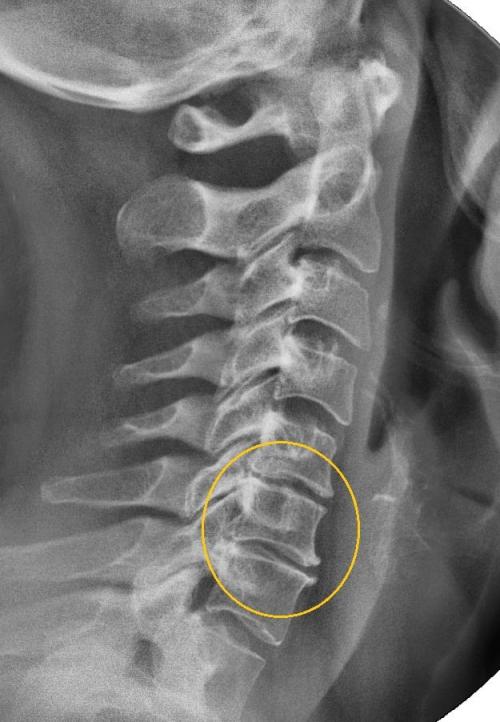

Хрустит и болит плечо при вращении. Шейный остеохондроз

Щелчки и боль при вращении плеча — один из симптомов шейного остеохондроза 2 или 3 степени тяжести. Для патологии характерно постепенное разрушение вначале хрящевых межпозвонковых дисков, а затем костных позвонков. Причинами развития патологии становятся серьезные физические статические и динамические нагрузки, эндокринные заболевания (тиреотоксикоз, сахарный диабет), травмы, естественное старение организма. От остеохондроза часто страдают люди, проводящие много времени за компьютером, печатной машинкой, микроскопом. Для патологии характерна выраженная и разнообразная симптоматика:

Диагноз на рентгене.

Появление щелчков в плече связано с деструкцией позвонков. Они уплощаются, разрастаются. Организм пытается стабилизировать позвонки, предупредить их смещение с помощью формирования остеофитов. Они, в свою очередь, сдавливают чувствительные окончания, провоцируя спазмы скелетной мускулатуры. Это снижает функциональную активность плечевого сустава, приводит к нарушению кровообращения и уменьшению выработки синовиальной жидкости.